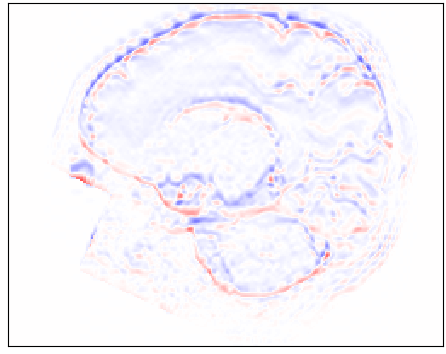

Figure 10: Qualitative comparison of image synthesis performance on neonatal brain MRI (dHCP dataset) between conventional interpolation methods and proposed approach. Original volumes with slice thickness and spacing of 0.5 mmtimes0.5millimeter0.5\text{\,}\mathrm{mm} were downsampled to 2.5 mmtimes2.5millimeter2.5\text{\,}\mathrm{mm} by applying a Gaussian blur before including every fifth slice in the test volume. Differences between reference (minuend) and synthesized slice (subtrahend). Blue corresponds to negative and red to positive differences. Image intensities are scaled to a [0,1]01[0,1] range. All difference images use the same color scale [1,1]11[-1,1].

Visual inspection of Figure 10 conveys that our proposed approach was able to synthesize excluded high-resolution axial slices more accurately than cubic B-spline interpolation. These results are corroborated by the coronal and sagittal views revealing that volumes generated by the proposed method are less blurry and contain smoother transitions between slices compared to volumes generated by the conventional interpolation method.